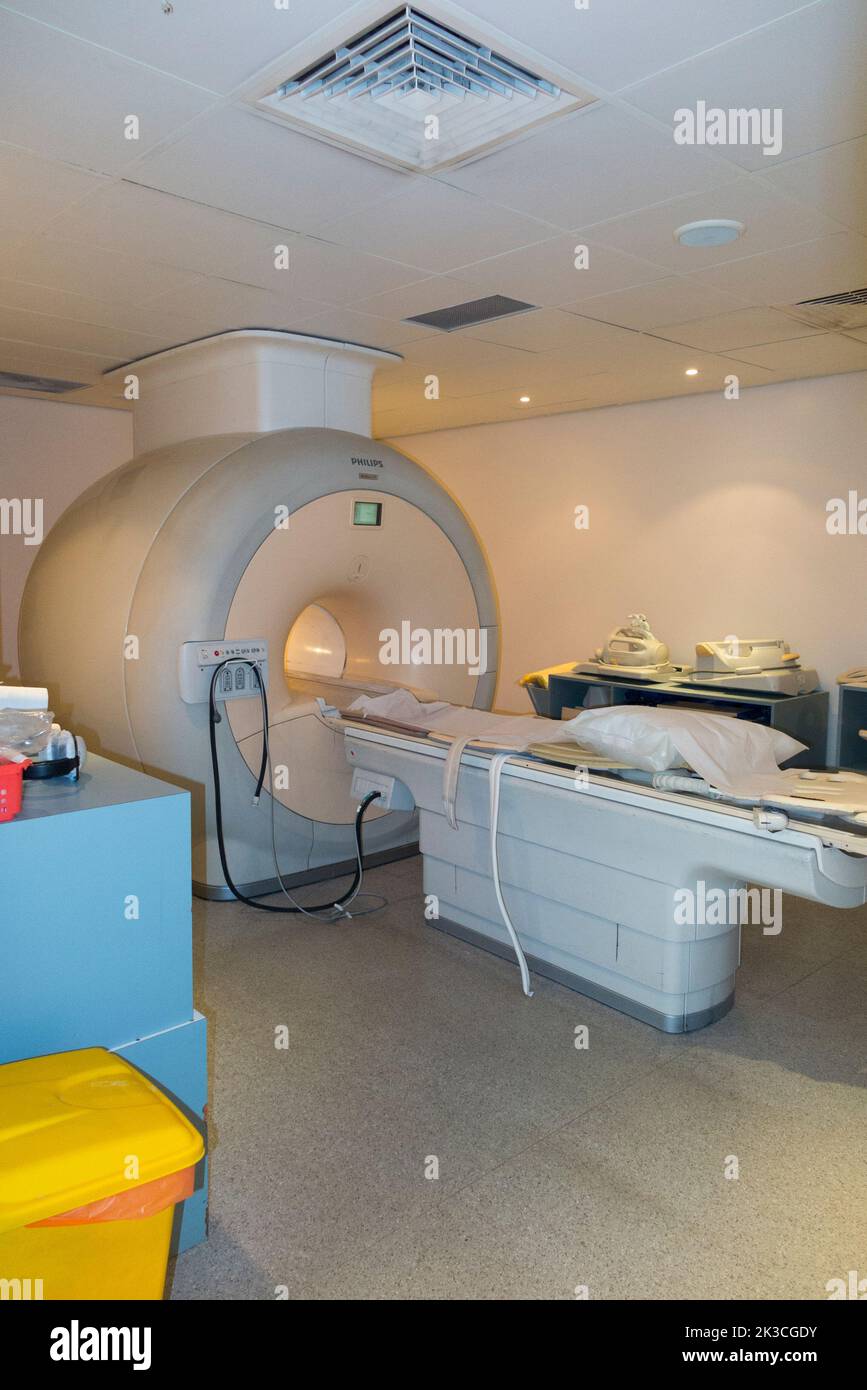

Un scanner IRM (considéré comme une machine IRM Philips Achieva) est un appareil IRM du corps entier destiné à l'examen des patients, dans un hôpital, utilisé pour les patients privés et non médicaux. Banque D'Imageshttps://www.alamyimages.fr/image-license-details/?v=1https://www.alamyimages.fr/un-scanner-irm-considere-comme-une-machine-irm-philips-achieva-est-un-appareil-irm-du-corps-entier-destine-a-l-examen-des-patients-dans-un-hopital-utilise-pour-les-patients-prives-et-non-medicaux-image484010631.html

Un scanner IRM (considéré comme une machine IRM Philips Achieva) est un appareil IRM du corps entier destiné à l'examen des patients, dans un hôpital, utilisé pour les patients privés et non médicaux. Banque D'Imageshttps://www.alamyimages.fr/image-license-details/?v=1https://www.alamyimages.fr/un-scanner-irm-considere-comme-une-machine-irm-philips-achieva-est-un-appareil-irm-du-corps-entier-destine-a-l-examen-des-patients-dans-un-hopital-utilise-pour-les-patients-prives-et-non-medicaux-image484010631.htmlRM2K3CGDY–Un scanner IRM (considéré comme une machine IRM Philips Achieva) est un appareil IRM du corps entier destiné à l'examen des patients, dans un hôpital, utilisé pour les patients privés et non médicaux.